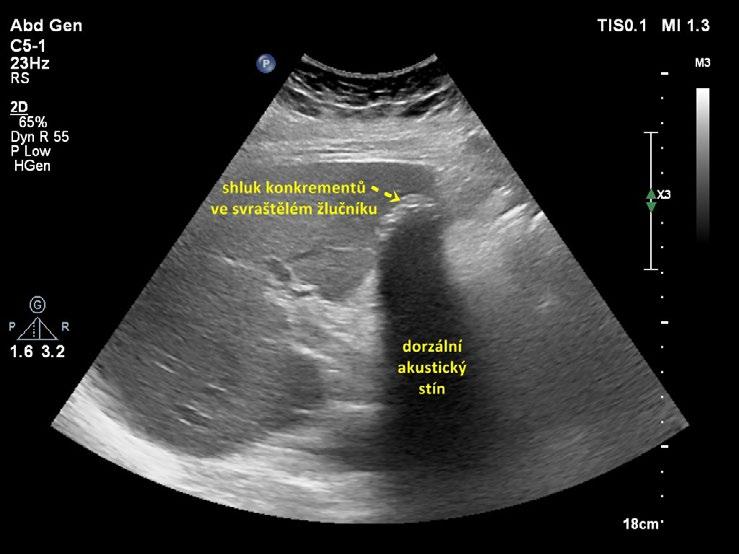

• svraštělý žlučník vyplněný konkrementy (obr. 1.13, obr. 1.14). Lumen ani stěna žlučníku nejsou patrny, v místě žlučníku je shluk konkrementů s dorzálním akustickým stínem. Tento nález je někdy popisován jako „nepřímá známka cholecystolitiázy“, protože pouze z lokalizace konkrementů v typickém místě uložení žlučníku lze dedukovat, že jde o cholecystolitiázu;

Obr. 1.14 Svraštělý žlučník vyplněný litiázou